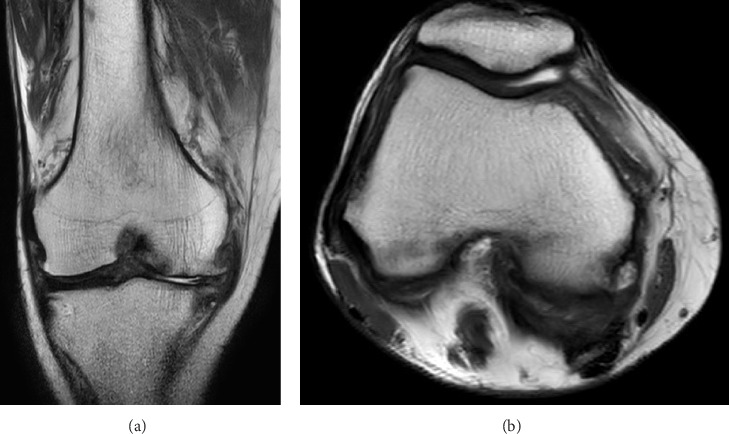

慢性髓单细胞白血病(CMML)是一种以单核细胞造血为主的骨髓增生性疾病。它有时并发皮肤受累,称为白血病皮肤,这与预后不良有关。我们报告了一位患有CMML的患者,他出现发烧并伴有膝关节肿胀和疼痛。患者被认为患有白血病性滑膜炎,阿扎胞苷治疗改善了她的症状。我们的病例提示白血病性滑膜炎可能是治疗的指征,对于出现关节肿胀的白血病患者应该进行关节穿刺。

Chronic myelomonocytic leukemia (CMML) is a myeloproliferative disease characterized by monocyte-predominant hematopoiesis. It is sometimes complicated with cutaneous involvement known as leukemic cutis, which is associated with a poor prognosis. We report a patient with CMML who developed fever with knee joint swelling and pain. The patient was considered to have leukemic synovitis, and treatment with azacitidine improved her symptoms. Our case suggested that leukemic synovitis might indicate the indication for treatment, and arthrocentesis should be performed in patients with leukemia who present with joint swelling.